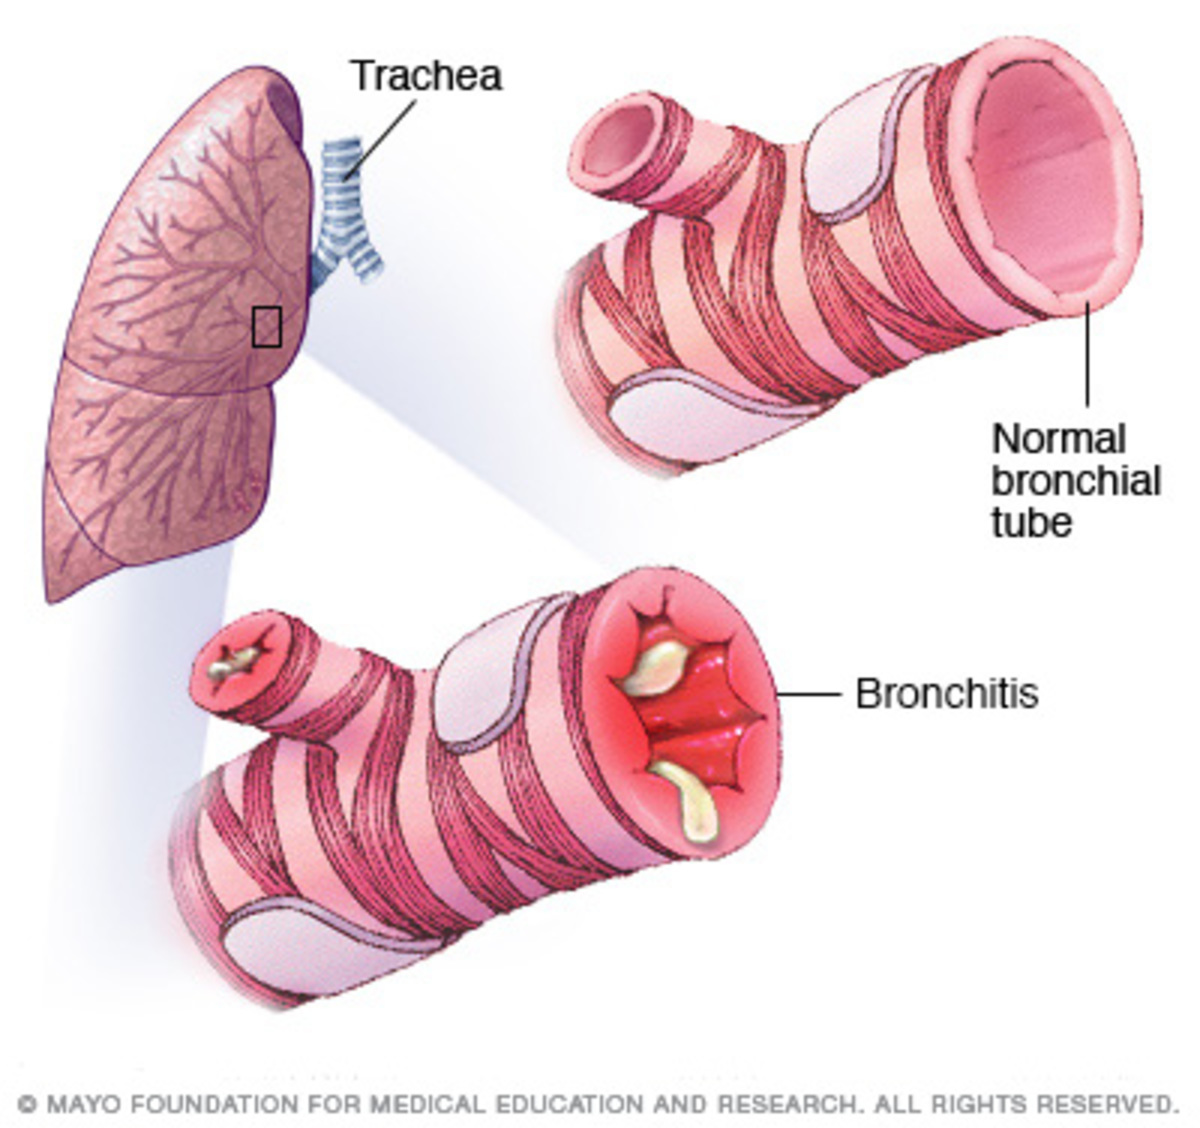

Οι άνθρωποι που έχουν βρογχίτιδα συχνά έχουν πτύελα με παχύτερη βλέννα και με διαφορετικό χρώμα από το κανονικό. Ως πάθηση, η βρογχίτιδα μπορεί να είναι οξεία ή χρόνια.

Η πρώτη συχνά αναπτύσσεται μετά από ένα “δυνατό” κρυολόγημα, ή άλλη αναπνευστική λοίμωξη. Η χρόνια βρογχίτιδα είναι μια πιο σοβαρή κατάσταση και αφορά τον διαρκή ερεθισμό, ή φλεγμονή του βλεννογόνου των βρόγχων, συχνά λόγω του καπνίσματος.

Η οξεία βρογχίτιδα συνήθως βελτιώνεται μέσα σε λίγες ημέρες χωρίς μόνιμες επιπτώσεις, αν και ο ασθενής μπορεί να έχει βήχα για μερικές εβδομάδες. Ωστόσο, αν έχετε επαναλαμβανόμενες κρίσεις βρογχίτιδας, μπορεί να έχετε τη χρόνια μορφή της, η οποία απαιτεί πιο επισταμένη ιατρική φροντίδα. Η χρόνια βρογχίτιδα είναι μία από τις προϋποθέσεις για την διάγνωση της Χρόνιας Αποφρακτικής Πνευμονοπάθειας (ΧΑΠ).